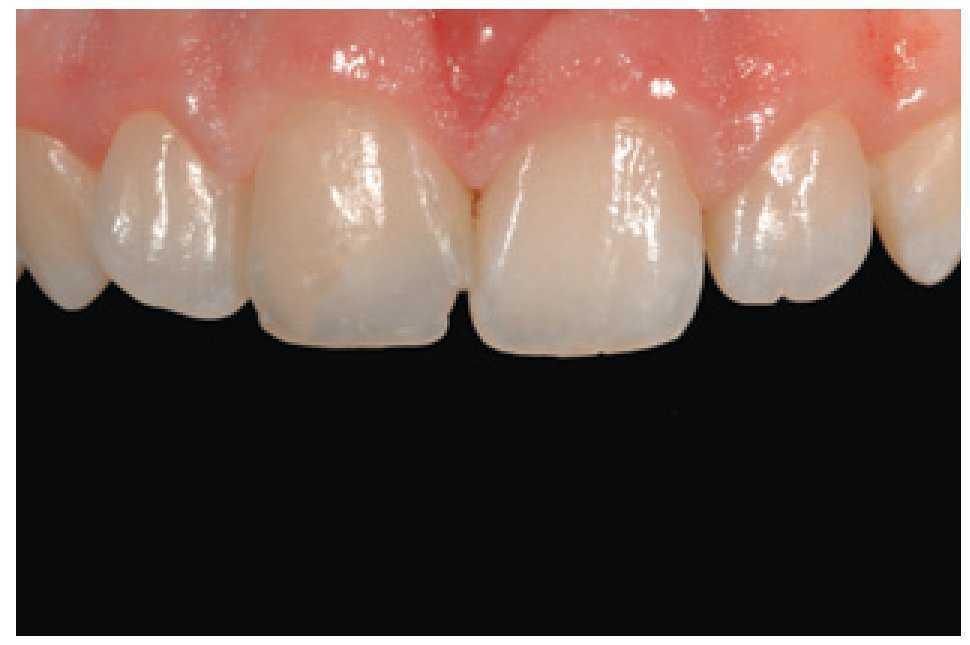

Figura 3 El caso terminado tras la reconstrucción con composite, realizada tras la cicatrización de los tejidos gingivales.